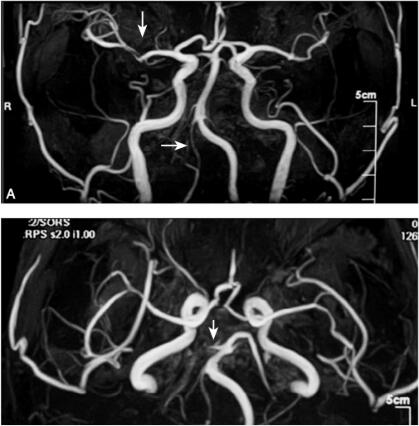

MRI弥散加权成像(DWI)(发病后1日):双侧大脑后动脉及左侧大脑中动脉供血区域的多发新鲜梗死灶,多处为皮层梗死灶(图1.12-1),MRI液体衰减反转恢复像(FLAIR):见脑桥及前后分水岭区陈旧小的梗死病灶。MRA:右侧大脑中动脉M1段远端可疑狭窄,右侧大脑后动脉P1段远端未显影,右侧椎动脉显影不良(图2)。

图2 磁共振血管成像(MRA):A.右侧大脑中动脉M1段远端可疑狭窄(纵向箭头),右侧椎动脉显影不良(横箭头);B.右侧大脑后动脉P1段远端未显影(箭头)